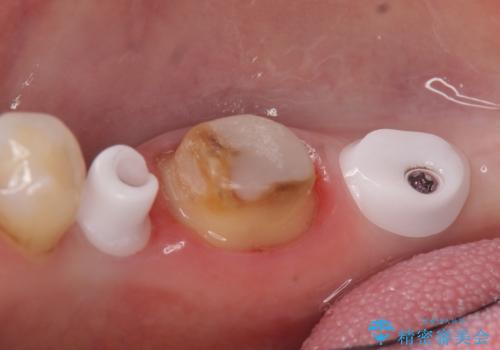

右下7は欠損しており、右下5は保存不可能だったため、インプラントによる欠損補綴を行いました。

インプラント埋入時には骨が不十分な部位に骨増生を行っております。